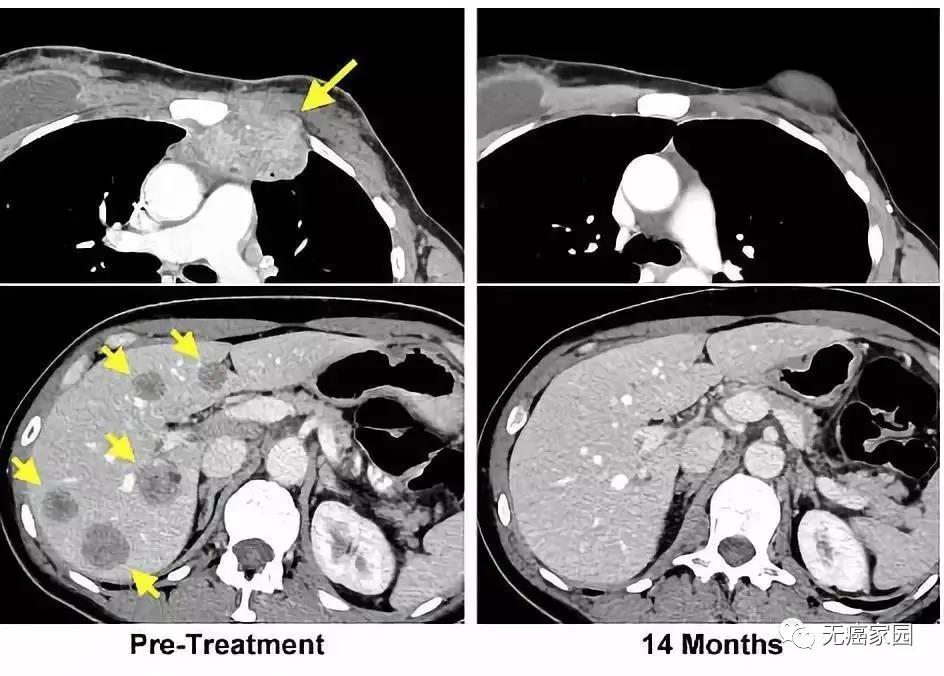

左图黄色箭头是治疗前肿瘤位置;右图是治疗结束14个月后的复查:肿瘤完全消失

一位晚期黑色素瘤患者肿瘤在治疗前出现广泛转移,在接受TILs疗法后一个月病灶明显缩小,治疗6个月达到完全缓解,治疗两年后仍然处于完全缓解状态,并且体内持续存在肿瘤反应性CD8+T细胞。